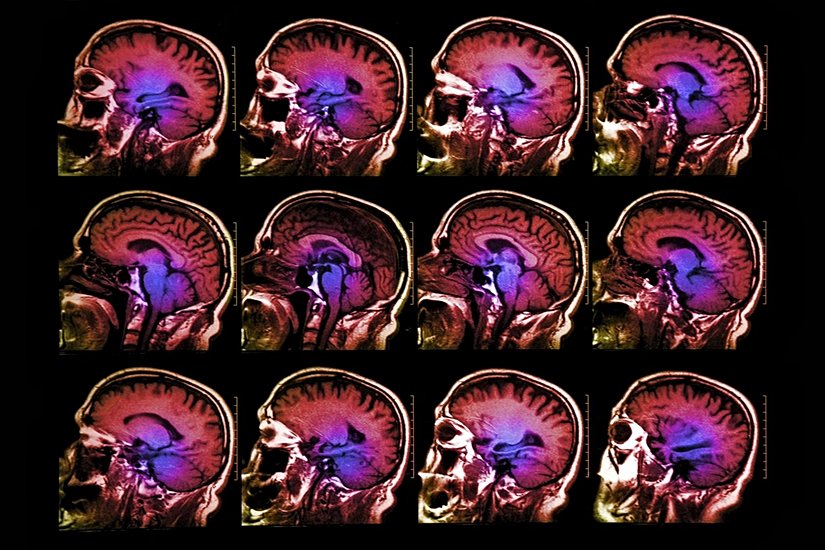

Nörobilim alanı yakın tarihimizde geliştirilen fMRI sayesinde hareketlendi. İnsanlar fMRI makinesinin içine uzandıkları zaman, bilim insanları kişinin gerçek zamanlı beyin aktivitelerini görebiliyor. Bu, beynimizin gri maddesi üzerindeki sırları açığa çıkaracağını vaat eden bir beyin okuma türüdür.

Önceki çalışmalarda tespit edilemeyen şey, kişinin aslında ne hissediyor olduğuydu. Carnegie Mellon Üniversitesi’nden açıklanan bir yeni araştırma ise, duyguların aslında sinirsel aktiviteye bağlı olduğunu haritalandırdı. Bu bunu yaparken de fMRI makinası kullanıldı.

CMU’nun Dietrich Beşeri ve Sosyal Bilimler Kolejinden araştırmacılar, deneyde kullandıkları aktörlere öfke, tiksinti, kıskançlık, şehvet, gurur, üzenti, utanç gibi kelimeleri gösterildi. Bundan sonra, aktörlere gördükleri kelimelerdeki duygusal hale gelmeleri istendi ve beyinleri fMRI tarafından görüntülendi ve bilgisayar tarafından sonuçlar çıkarıldı.

Bu taramaya göre, bilgisayar, duyguları anımsatacak seri fotoğraflarını gören aktörlerin duygularını düzgünce tahmin edebildi. Her duygunun özel bir sinirsel imzası bulunmaktadır. Bilgisayarın öğrendiği beyin aktivitesinin desenleri bu bireylerle sınır değil. Aktörlerin beyinlerinin taramasına göre, bilgisayar model teste daha önce hiç girmemiş olan yeni aktörlerin duygularını aydınlattı.

Yeni araştırma duyguların objektif bir şekilde ölçülmesine bir temel oluşturuyor. “Beyinde aktif olan farklı desenlerin pozitif ve negatif duygular olmak üzere ayrıldığını fark ettik.” diyor Kassam. Beynin duygusal yapıtaşları modeli oluşturarak, araştırmacılar duygusal rahatsızlıklardaki düşüncenin farkının ne olduğuna dair bir bakış açısı kazanabildi.